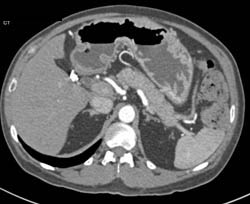

Diagnosis

Gastritis